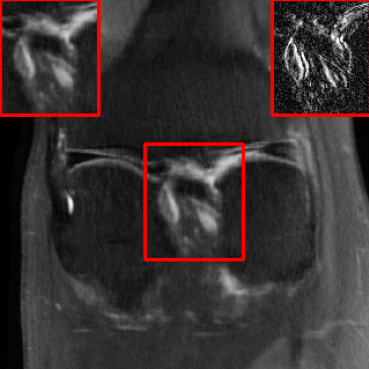

Performance on the Stanford FSE Dataset: We also performed image reconstructions with the Stanford multi-coil FSE dataset, which is a smaller dataset. We used same settings for the networks and training as in Section IV-A. Table III shows that LONDN-MRI significantly outperforms the globally learned MoDL network at both 4x and 8x acceleration. This indicates benefits for the proposed framework for smaller, more diverse datasets. Figs. 7 and 8 display visual comparisons that show the LONDN-MRI scheme recovering sharper features than the globally learned network.

| Ground Truth | Initial | Global | LONDN-MRI | LONDN-MRI | Oracle |

| (1 iteration) | (2 iterations) | ||||

![]() |

| PSNR = dB | PSNR = 22.01 dB | PSNR = 29.02 dB | PSNR = 31.46 dB | PSNR = 31.74 dB | PSNR = 31.87 dB |